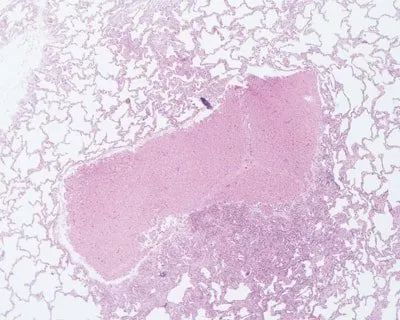

圖示為腫塊脫水切片薄(2-3mm)且均一。此切片能進行有效的脫水并且易于切成蠟片。

H&E染色的肺:使用鉗子隨意夾取組織,引起組織局部有明顯的損傷。新鮮的或者固定不充分的組織很容易受損,即使是一些固定充分的組織也會因隨意夾取而受損。

H&E染色肺:含有肝的碎屑,在取材過程中被污染的。